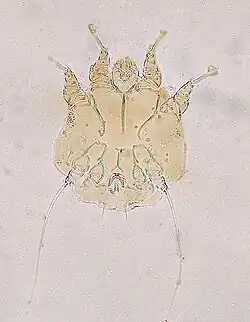

Most commonly N. cati as a cause of Notoedric mange may be diagnosed from a skin scraping sample with a direct microscopic identification of the mite, because there are a large number of mites present on the skin. Characteristic and systemic symptoms of Notoedric mange also help with diagnosis.[12]